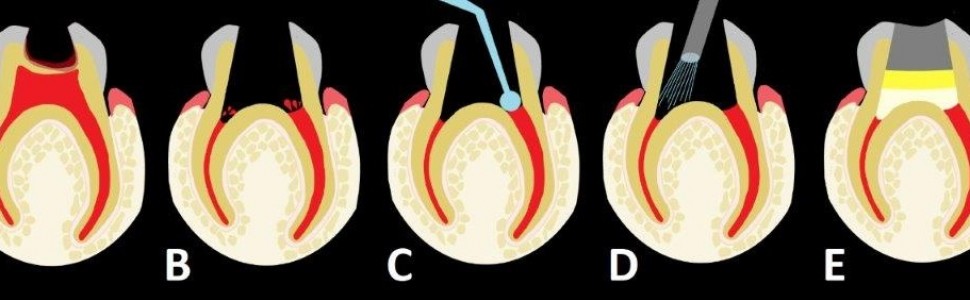

Rycina 1 prezentuje poszczególne etapy amputacji z użyciem siarczanu żelaza, a ryc. 2 to zdjęcia wykonane u 2,5-letniej pacjentki w trakcie zabiegu amputacji miazgi z zastosowaniem preparatu zawierającego w swoim składzie siarczan żelaza (20% siarczan żelaza, Pulpogel, Chema-Elektromet).

Ryc. 1. Ząb z próchnicą głęboką powikłaną. A. Próchnica penetruje do miazgi, niszcząc sklepienie komory zęba; B. Stan po całkowitym opracowaniu ubytku, zdjęciu sklepienia komory i odcięciu miazgi na wysokości ujść kanałów; widoczne krwawienie z kikutów miazgi pozostawionych w obrębie kanałów; C. Wcieranie w krwawiącą miazgę preparatu zawierającego siarczan żelaza; D. Wypłukanie sprayem wodno-powietrznym brunatnych skrzepów powstałych w wyniku reakcji żelu z krwią; E. Stan po przykryciu miazgi kanałowej cementem tlenkowo-cynkowo-eugenolowym, założeniu podkładu oraz odbudowie korony materiałem plastycznym.